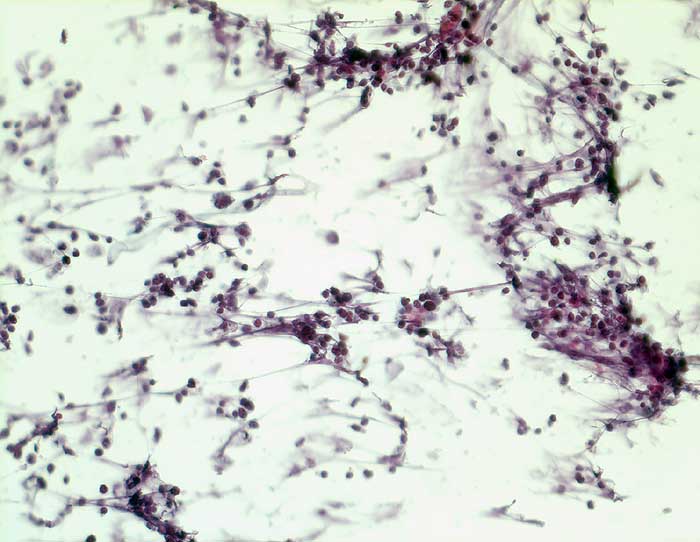

Die Tumorzellen des kleinzelligen Karzinoms erscheinen in der Übersicht eher einförmig. Bei stärkerer Vergrösserung zeigt sich aber eine deutliche Polymorphie. Die Kerne sind rundlich, eckig oder spindelig und je nach Erhaltungszustand mehr oder weniger hyperchromatisch. Der Kernhintergrund ist dunkel und das Chromatin fein dispers. Nukleolen sind meist unscheinbar. Plumpe grosse Nukleolen sprechen eher für ein grosszellig neuroendokrines Karzinom, dessen Morphologie im Übrigen mit derjenigen des kleinzelligen Karzinoms überlappt. Die Abgrenzung von einem Lymphom oder aktivierten Lymphozyten kann schwierig sein.